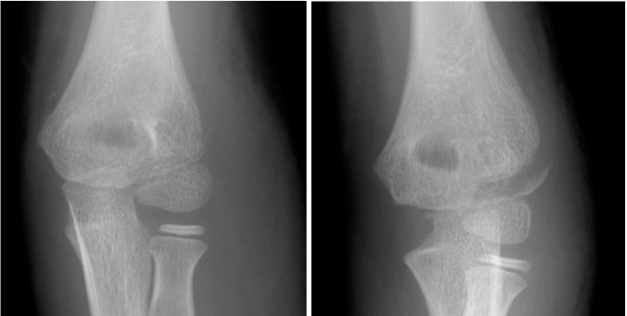

骨不连

最主要并发症,定义为伤后12周骨折未愈合,发生率1%-5%;诱因包括漏诊、非手术治疗迟发移位、手术治疗再移位/固定后残留移位>1mm;临床表现为肘外侧压痛、外翻畸形、肘关节活动受限;治疗依移位程度选择,轻度移位可行经皮加压螺钉固定(伤后16周内手术效果佳),重度移位需切开复位+植骨,合并外翻畸形者需联合截骨矫正。

图19 一名 13 岁男性患者,7 年前左肘关节骨折曾行石膏固定治疗;A 正位 X 线片示肱骨外髁骨折不愈合;该患者肘关节活动度正常,但存在疼痛症状,且疼痛限制了其体育运动。B 侧位 X 线片示骨折块对位异常(呈屈曲位)。C 行原位钢板固定联合髂骨植骨术后的正位 X 线片。D 术后侧位 X 线片。